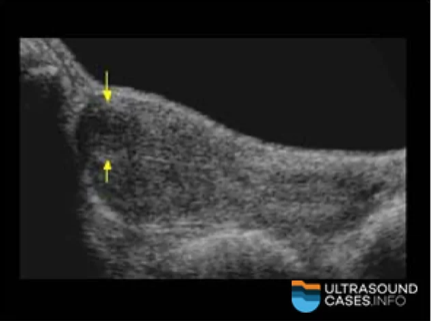

Where is the fibroid located in the image?

a. subserosal

b. intramural

c. submucosal

d. intracavitary

Submucosal